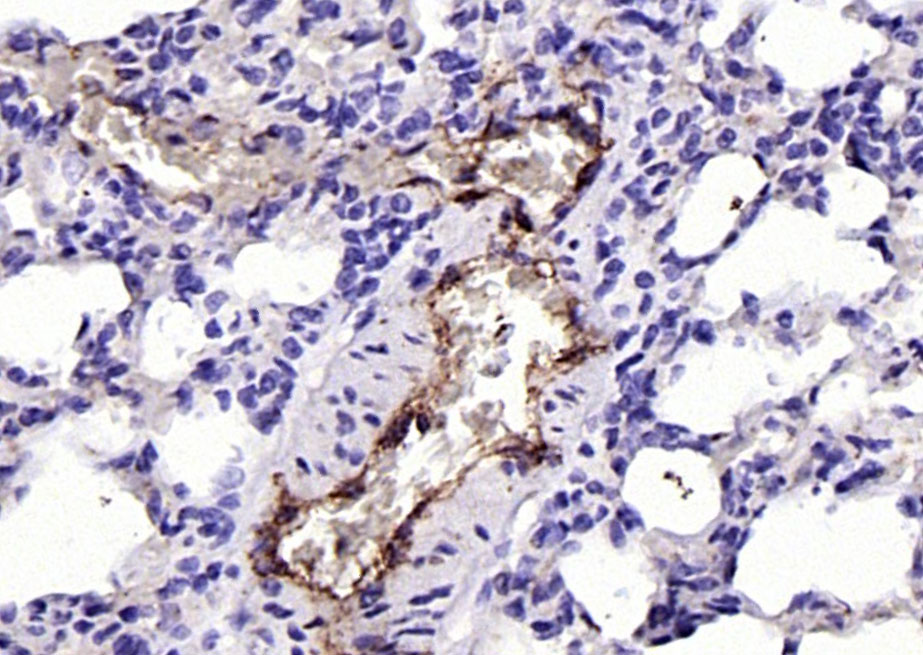

Cancer > Invasion/microenvironment > Angiogenesis > Angiogenic growth factors

Cardiovascular > Angiogenesis > Endothelial Cell Markers

| IHC-P | Human, Rat | Mouse | 1:100-500 |